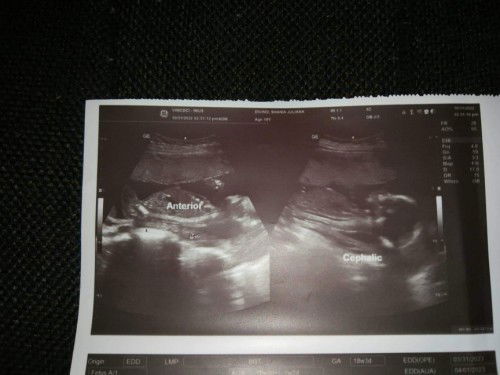

cephalic position

hello mommies normal lang ba na cephalic na si baby? 19 weeks na bukas.

Yes po mi, mas gusto mo pong cephalic ang position ni baby. Ibig sabihin nyan yung ulo ni baby nasa may cervix mo. Kabaligtaran po nyan is breech (suhi).

same experience mamsh .. anterior dn at naka cephalic n si baby at 6 months